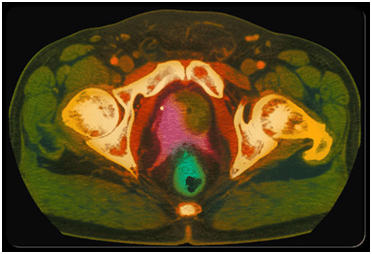

MRI SCAN/PET SCANS will help diagnose the stage of disease.